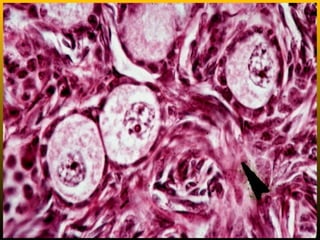

Follicular atresia or Degeneration

• Such degenerate follicles are called atretic

follicles. Sometimes they appear to contain a

dark pink-staining material which is probably the

remains of the zona pellucida of the follicle.

1. Oocyte showing signs of degeneration (multiple stages of this).

2. Stratum granulosa showing signs of disorganization.

3. Follicular cells separate from basal lamina and oocyte.

4. Glassy membrane (between granulosa and theca interna) is a

sign of advanced atresia.